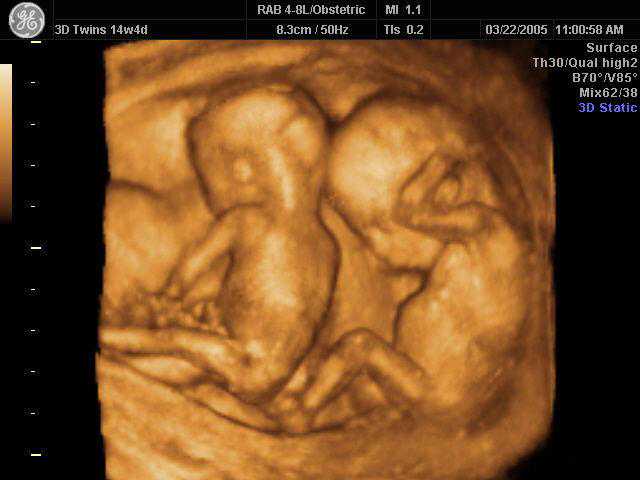

8.孕13-27周均属于中期妊娠。在此期间可以检测胎儿的生长发育情况,了解胎儿构造及羊水胎盘情况。

最后来个可爱的四维照!

有没有觉可爱到爆!